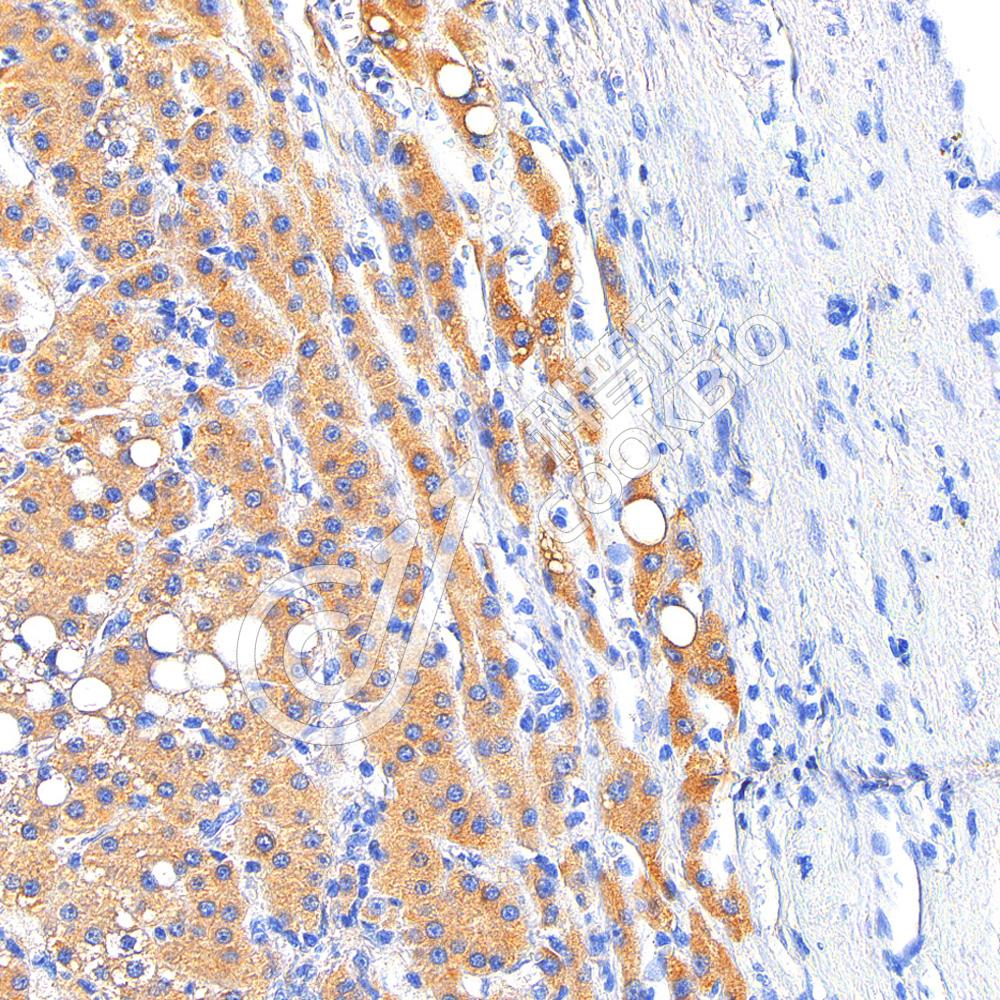

IHC检测Myeloperoxidase蛋白(货号 K2360048).

样品: 大鼠lps(6h)诱导肝脏炎症模型, 4%多聚甲醛 (货号KSG1101) 固定12-24小时.

抗原修复: 柠檬酸抗原修复液(干粉, pH 6.0) (KSG1201), 高压锅均匀喷气计时2分钟.

—抗: 1: 1000稀释, 4℃ 孵育过夜.

二抗: S-vision免疫组化多聚二抗(山羊抗小鼠), 即用型(货号KB3903), 室温孵育20分钟.